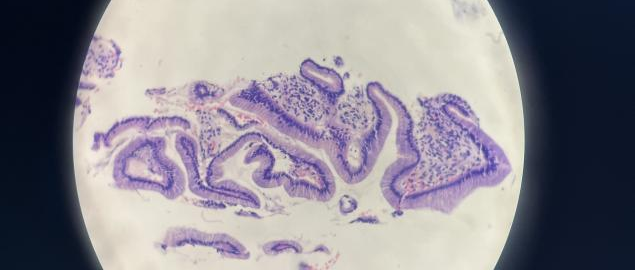

接下来,要把它放入全自动HE染色机中给它“穿上彩色的衣服”。(这个过程需要持续5-7小时左右)

最后,经过不同资历的病理医师在显微镜下进行初诊及复诊以后,就变成了一张最终的报告单。(正常情况下,常规病理报告出具的时间是3天,然而,如果遇到疑难特殊病例需要进行免疫组化或特殊染色辅助诊断时,报告时间就会顺延6-7天)